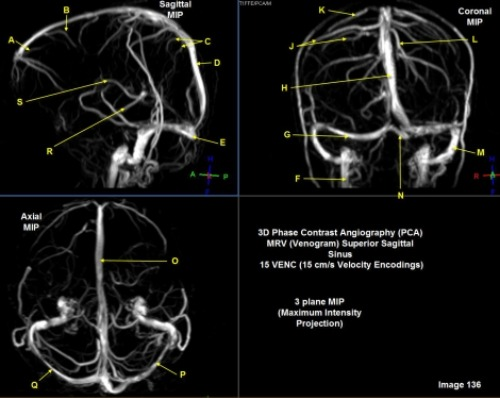

Letter C in Image 136 is pointing to:

C. Parietal veins

Letter Q in Image 136 is pointing to:

A. Right transverse sinus

Letter F in Image 136 is pointing to:

D. Internal jugular vein

Letter D in Image 136 is pointing to:

D. Superior sagittal sinus

Letter J in Image 136 is pointing to:

C. Right parietal veins

Letter M in Image 136 is pointing to:

F. Left sigmoid sinus

Letter R in Image 136 is pointing to:

F. A and / or C

Letter P in Image 136 is pointing to:

B. Left transverse sinus

Letter G in Image 136 is pointing to:

D. Right transverse sinus

Letter K in Image 136 is pointing to:

E. Vein of trolard

Letter E in Image 136 is pointing to:

C. Torcular herophili

Letter B in Image 136 is pointing to:

B. Posterior frontal vein